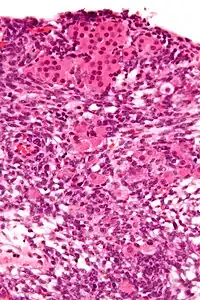

Micrograph of a Sertoli–Leydig cell tumour. The Leydig cells have abundant eosinophilic or light pink cytoplasm. The Sertoli cells have a pale/clear cytoplasm. H&E stain.

The tumour is subdivided into many different subtypes. The most typical is composed of tubules lined by Sertoli cells and interstitial clusters of Leydig cells.